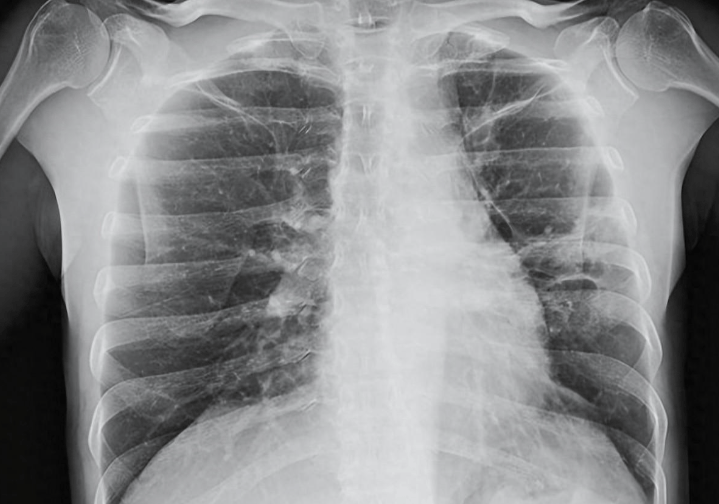

舒沃哲®由迪哲医药自主研发,是全球唯一获批治疗表皮生长因子受体(EGFR)20号外显子插入突变(exon20ins)非小细胞肺癌(NSCLC)的口服小分子靶向药。凭借独特的创新分子结构设计,舒沃哲®从源头突破了EGFR exon20ins靶点"难成药"的困局,填补了近20年临床治疗空白。在临床应用中,舒沃哲®突破既往治疗瓶颈,展现出高效低毒、安全可控的治疗优势,为患者带来显著的临床获益。其创新分子设计和转化科学研究成果荣登肿瘤学权威期刊《Cancer Discovery》,注册临床研究成果被收录于《柳叶刀•呼吸医学》《临床肿瘤学期刊》等国际顶级期刊,获得国际学术界的高度认可。

2023年8月,舒沃哲®率先在中国获批上市;2024年被纳入《CSCO非小细胞肺癌诊疗指南》成为二/后线治疗EGFR exon20ins NSCLC唯一Ⅰ级推荐方案,并进入2024版中国国家医保目录,成为该领域唯一获批且可医保报销的药物,大幅提升患者用药可及性;2025年,舒沃哲®获美国食品药品监督管理局(FDA)批准上市,成为中国首个独立研发在美获批的全球首创新药,并同步纳入美国国立综合癌症网络(NCCN)非小细胞肺癌指南,标志着中国源头创新真正实现从"中国出发"到"全球认可"的关键跨越。